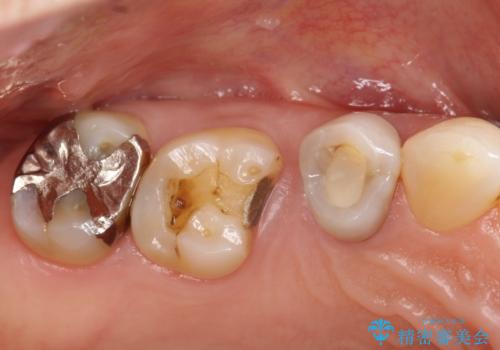

- 以前詰めた、インレーが外れたことを主訴に来院されました。

隣の歯にも虫歯を認めたためまとめて治療を行いました。

辺縁隆線にクラックラインを認め、破折防止のためにクラウンによる治療を希望されました。